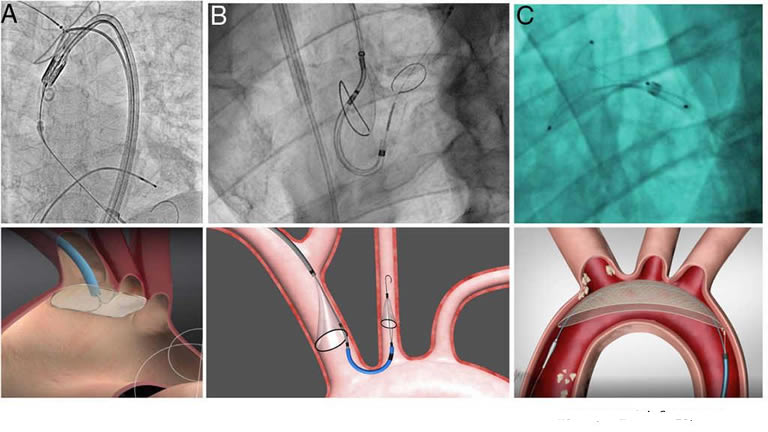

En Hospital Puebla, los Paquetes de Turismo Médico, incluyen la mejor oferta médica en Colocación TAVI, que es un procedimiento de mínima invasión, donde se inserta una nueva válvula cardíaca sin extraer la válvula dañada anterior. La nueva válvula se coloca adentro de la válvula dañada. El reemplazo de válvula tradicionalmente se realiza a través de una cirugía a corazón abierto, donde se abre el pecho quirúrgicamente para el procedimiento. . La diferencia con el TAVI es que éste se realiza a través de aberturas muy pequeñas en brazo o ingle, por lo que no es necesario cortar ningún hueso del pecho.